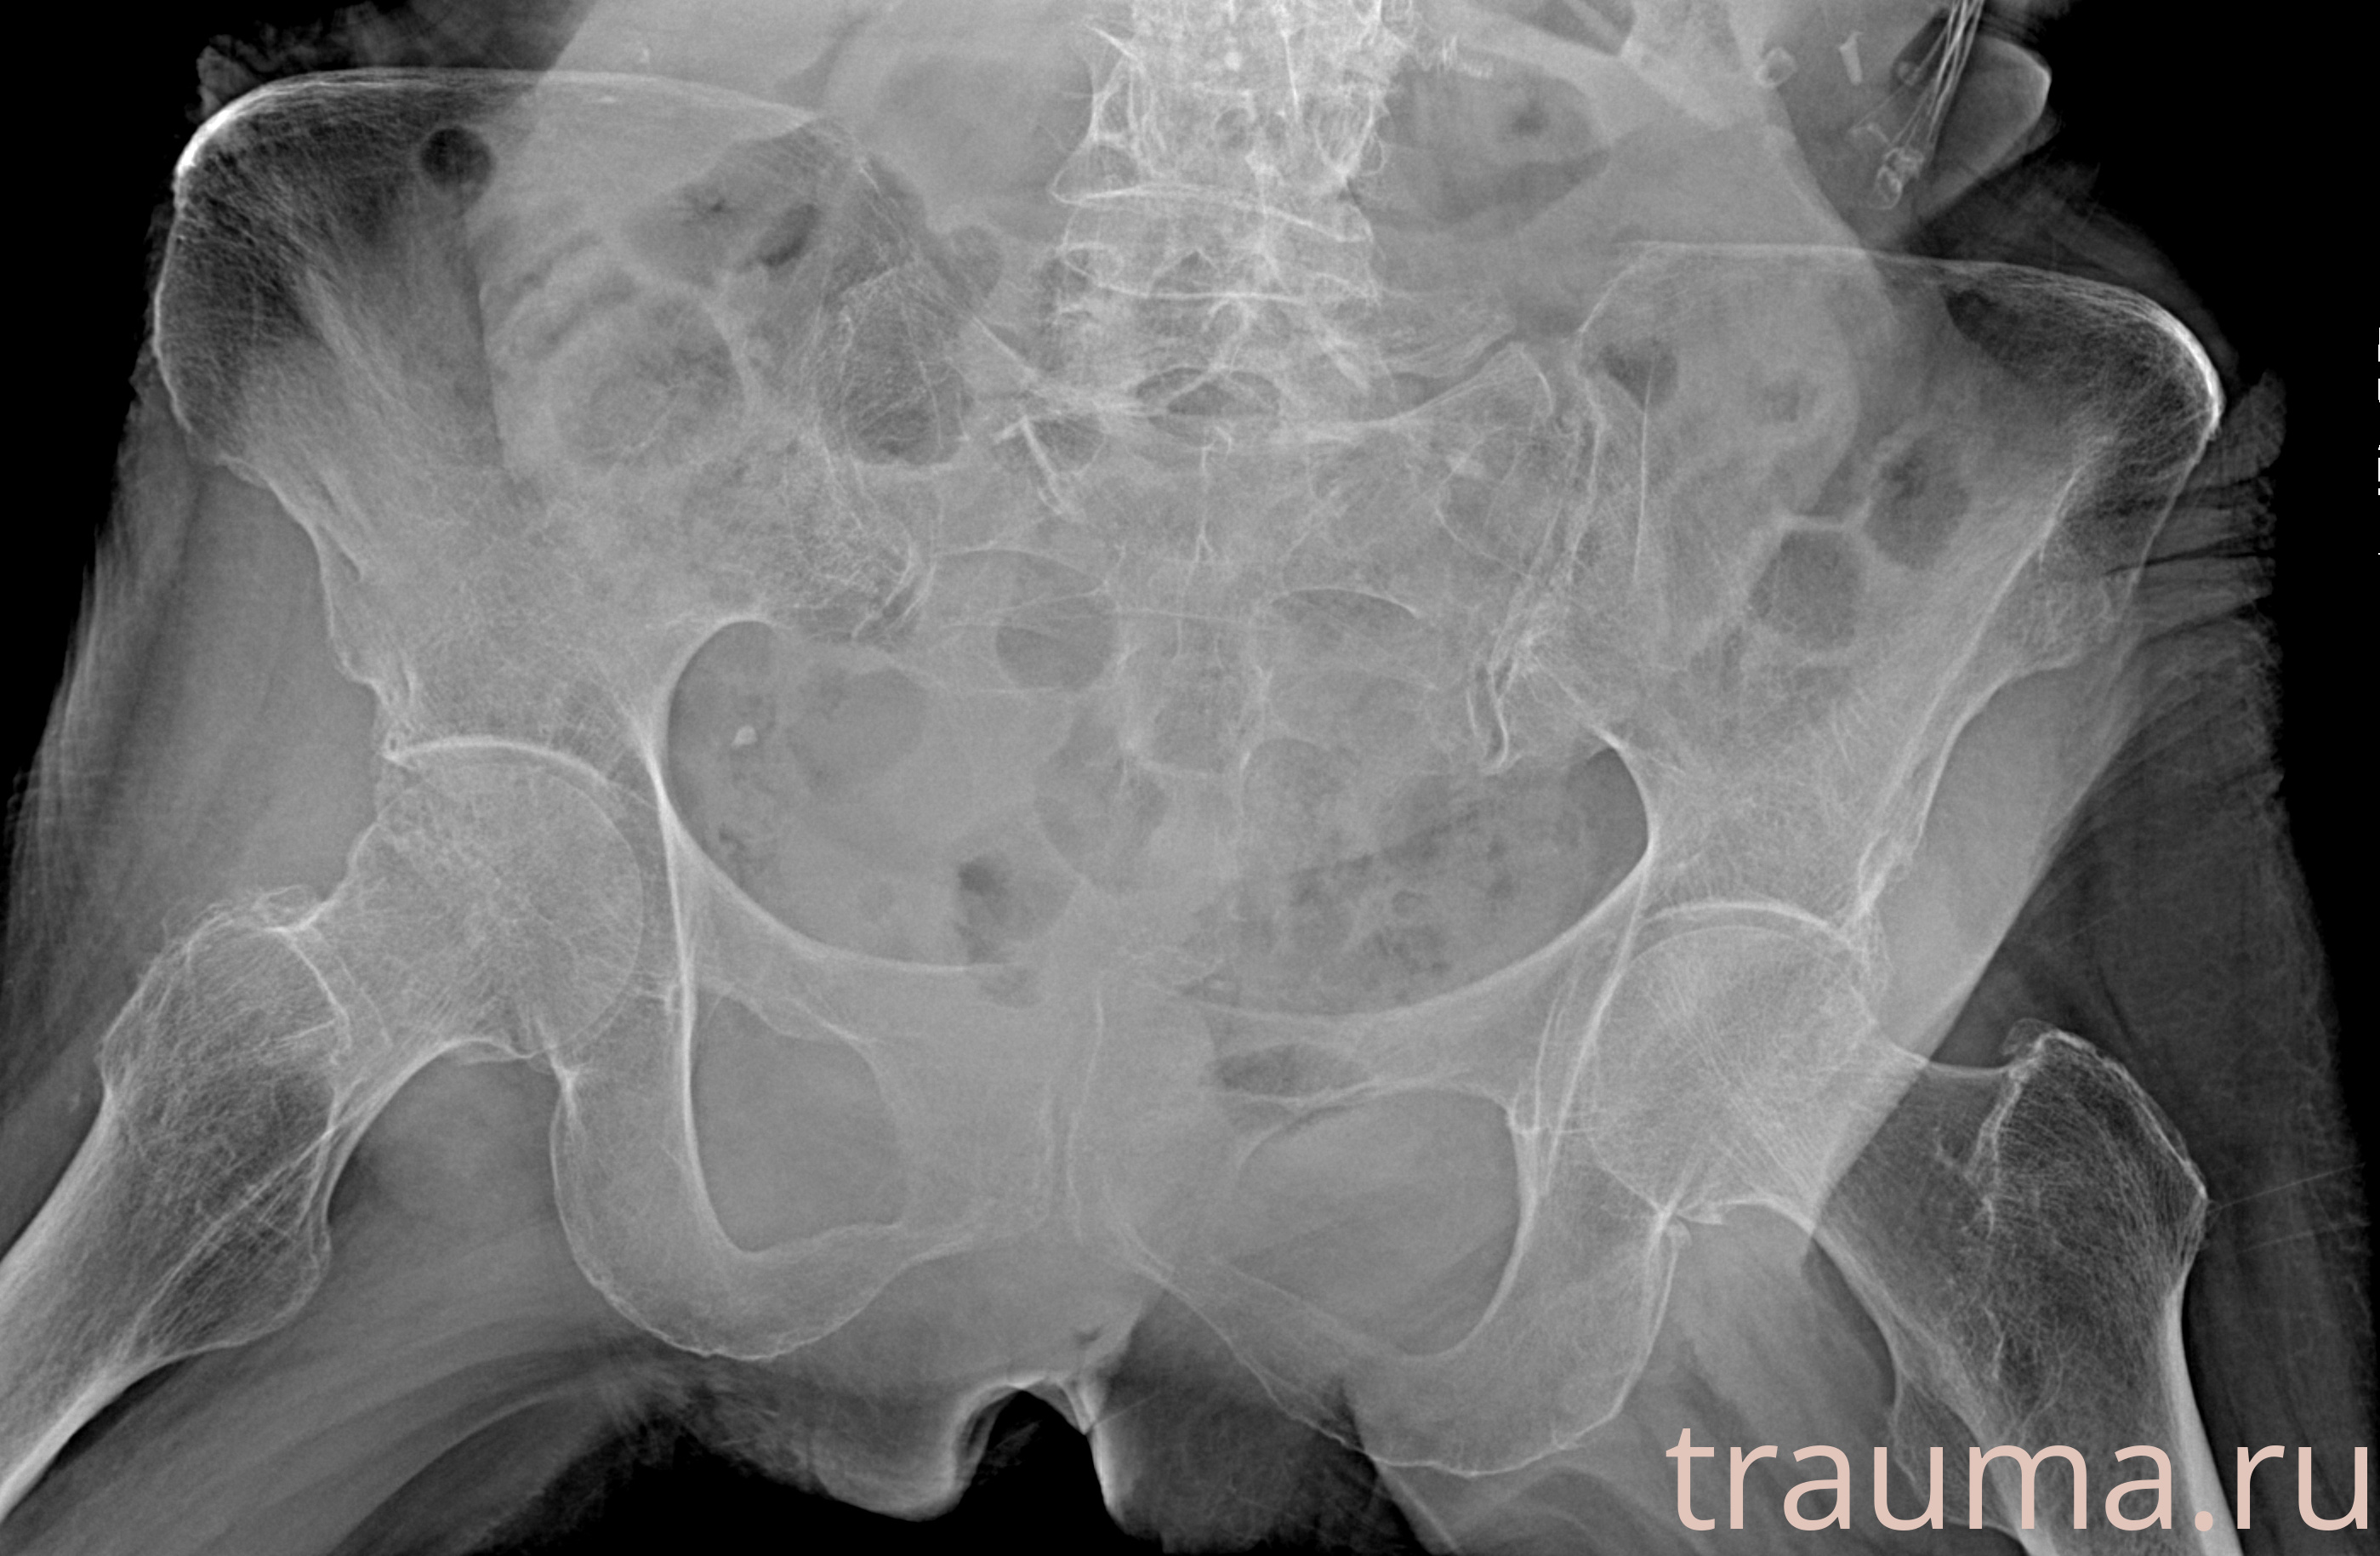

Рентгенограммы

Рентген на дому: по вашему адресу приезжает врач-рентгенолог, травматолог-ортопед с мобильным рентгеновским аппаратом, проводит диагностику травмы или заболевания, делает необходимые рентгенограммы, дает рекомендации по дальнейшему лечению. Получить качественные снимки в домашних условиях возможно благодаря уникальной методике, разработанной МосРентген Центром для института  Склифосовского